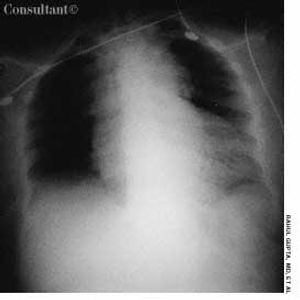

A 67-year-old woman presented to the emergency department (ED) with severe, sharp, central chest pain of sudden onset and mild shortness of breath. The pain had been present for 15 minutes. The patient was obese; her medical history included hypertension, myocardial infarction, and osteoarthritis.